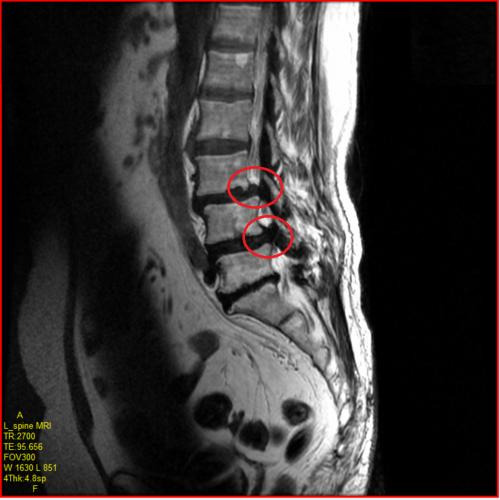

척추관 협착증은 단순 증상만으로는 다른 척추 질환과 구분하기 어렵기 때문에, 정확한 진단을 위해 영상 검사가 필수입니다.

- MRI: 신경이 눌리는 부위와 압박 정도를 가장 정밀하게 파악할 수 있는 검사입니다.